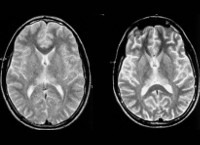

A81 Медленные вирусные инфекции центральной нервной системы